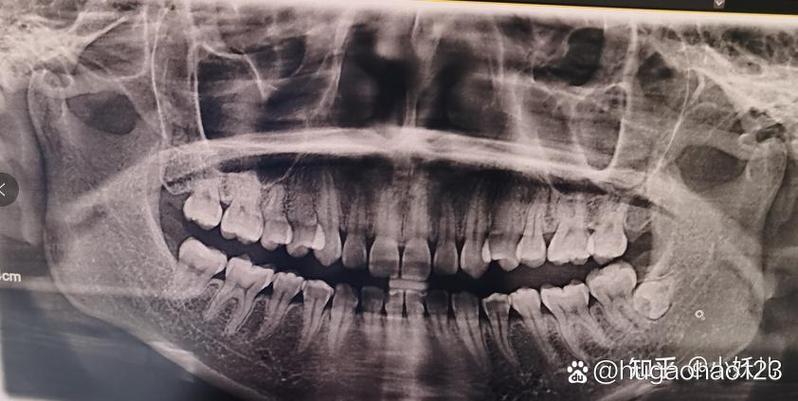

- 关键一步:拍片,医生会根据情况建议您拍摄牙片(小牙片)或CBCT(锥形束CT)。

- 小牙片:只能显示二维的牙根和骨头的位置,对于简单、位置较浅的智齿足够。

- CBCT:强烈建议拍!它能360度无死角地展示智齿与下颌神经管、邻牙牙根的精确关系,是判断手术难度和风险的最重要依据,也是制定手术方案的“地图”。